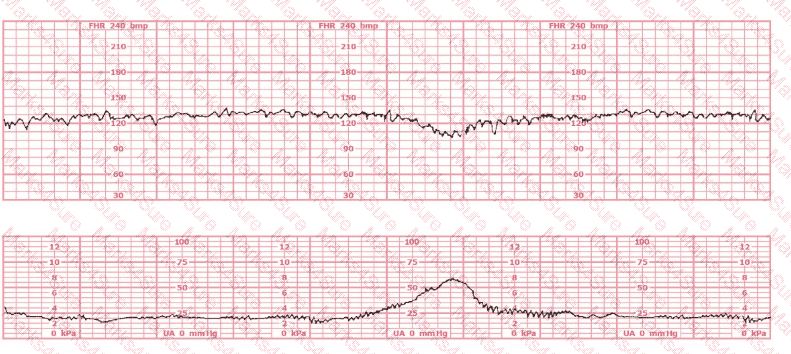

This fetal heart rate tracing is obtained upon the woman's admission to labor and delivery. This tracing is most reflective of:

A woman at 39-weeks gestation is in early labor, 2–3 cm dilated, 85% effaced, and –2 station. Based on the fetal heart rate tracing shown, what is the most appropriate first intervention?